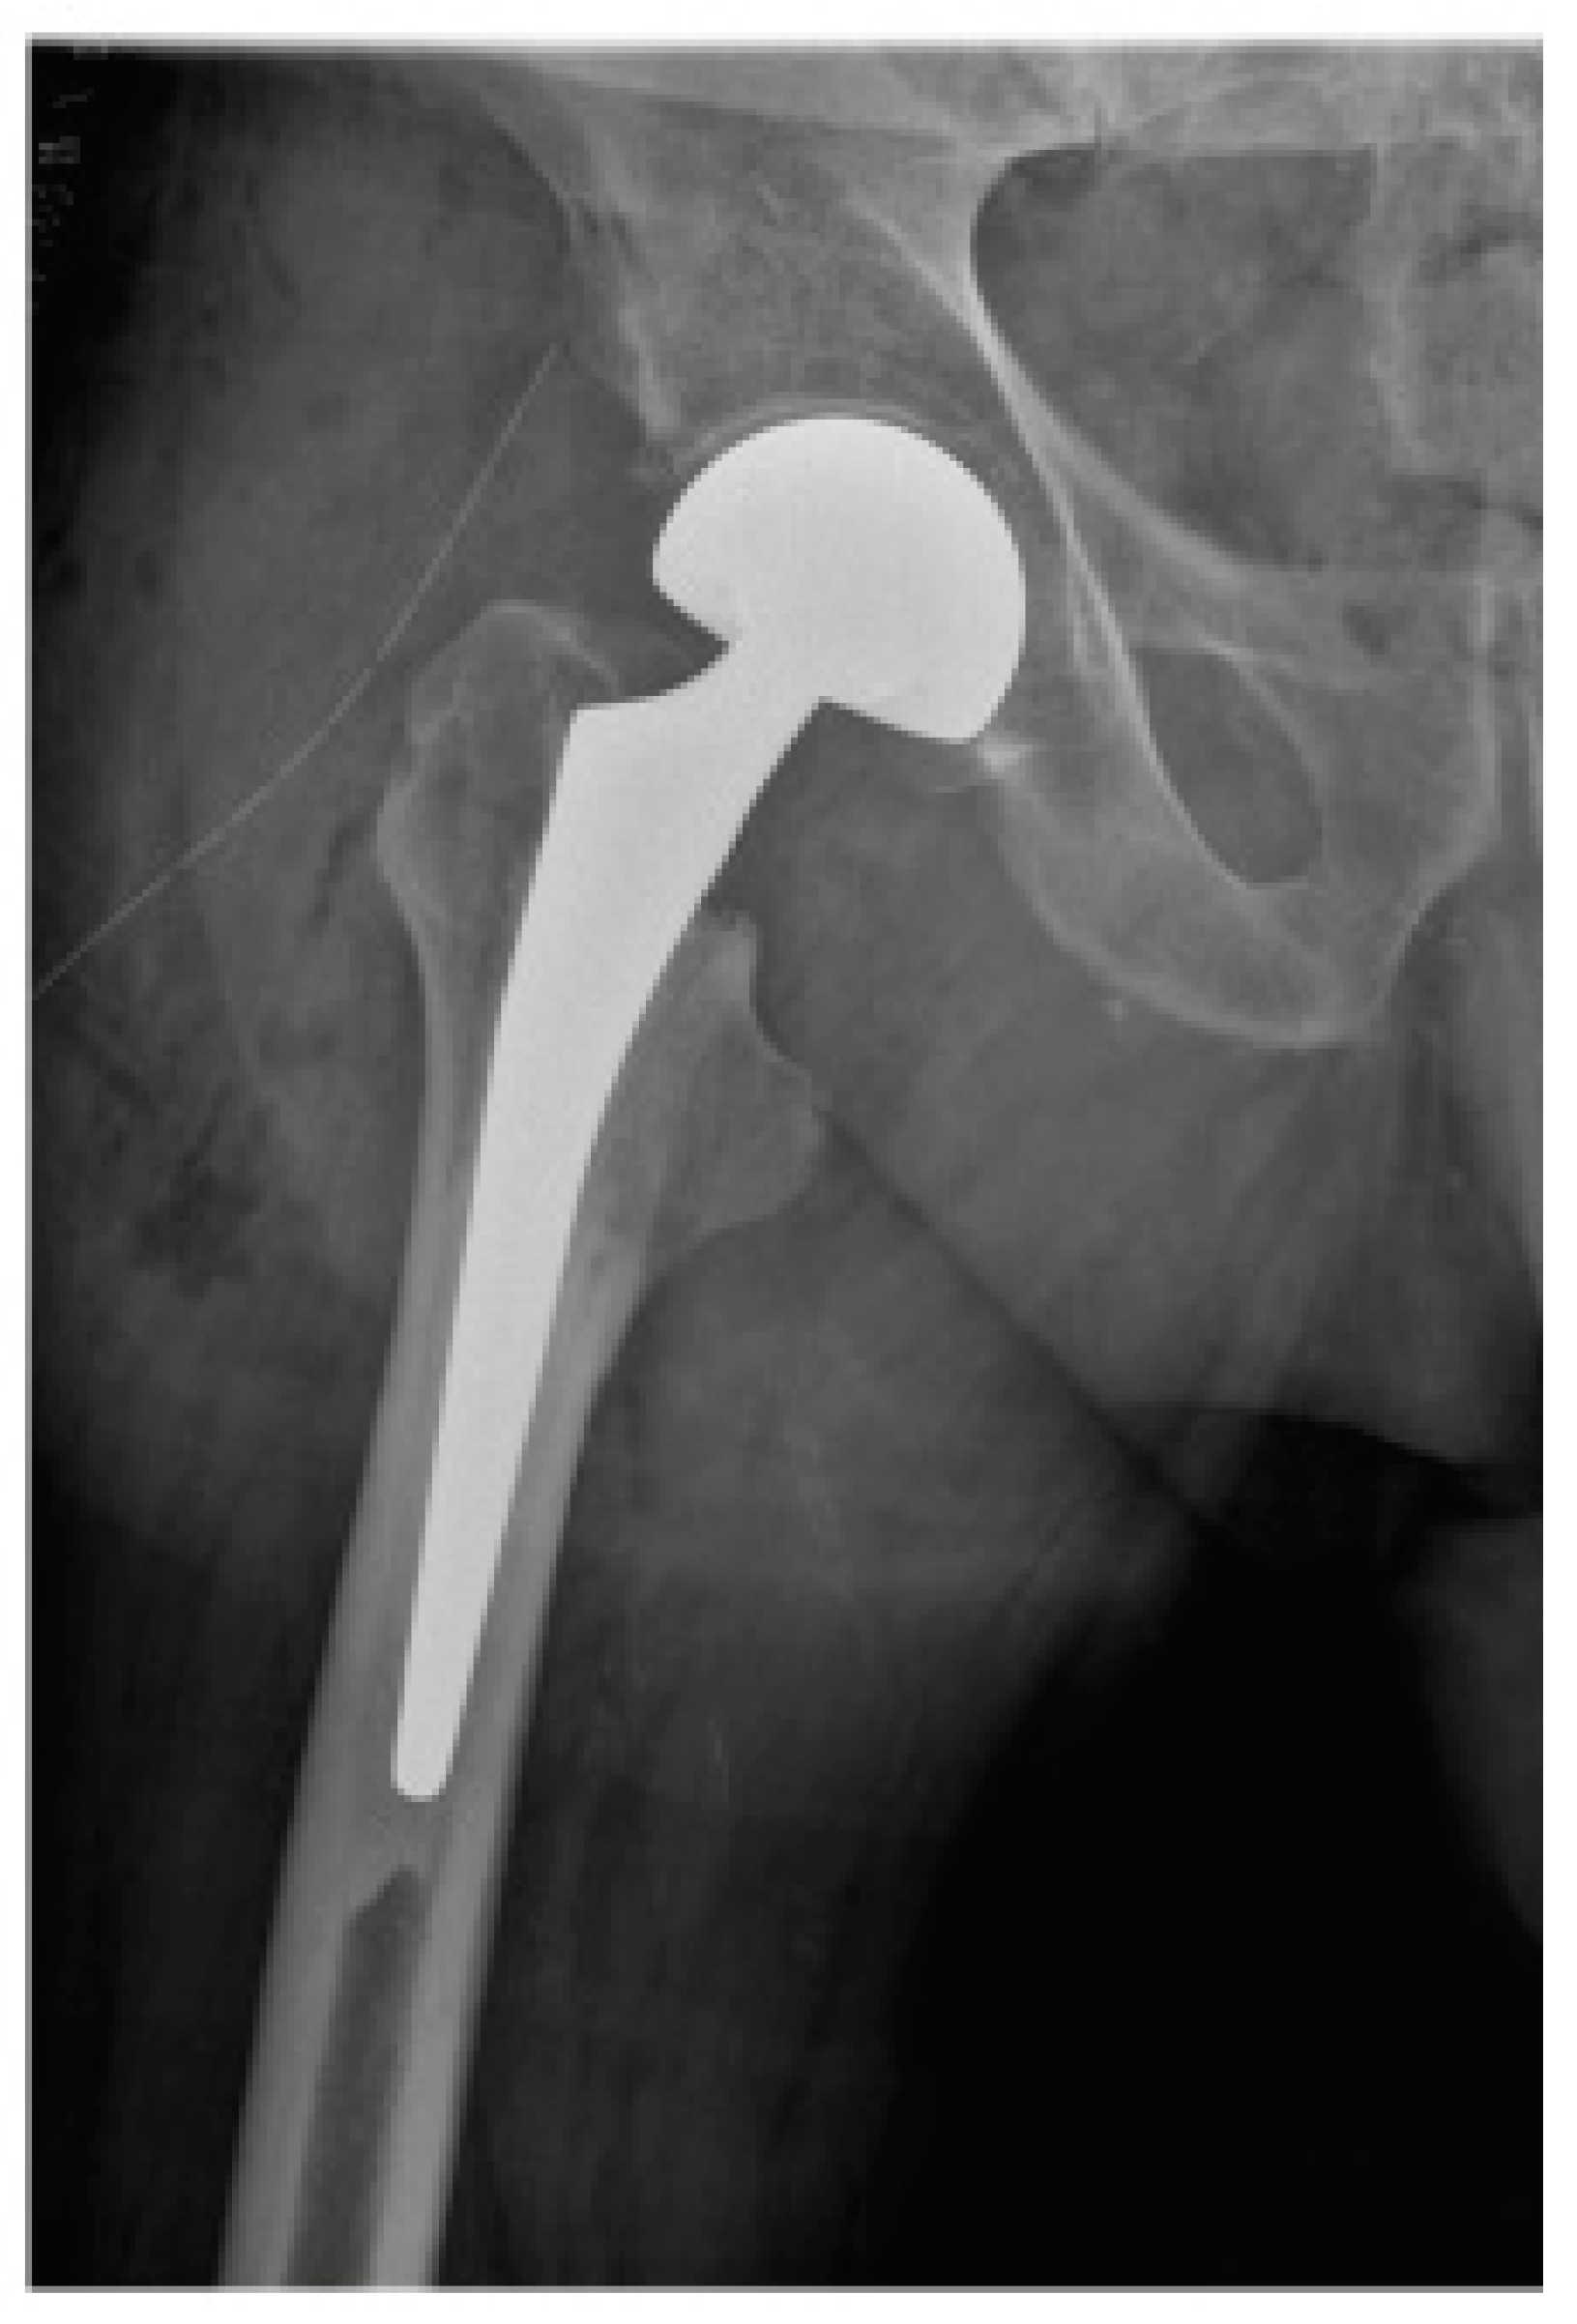

Early Postoperative Weight-Bearing Ability after Total Hip Arthroplasty versus Bipolar Hemiarthroplasty in Elderly Patients with Femoral Neck Fracture

2. Materials and Methods